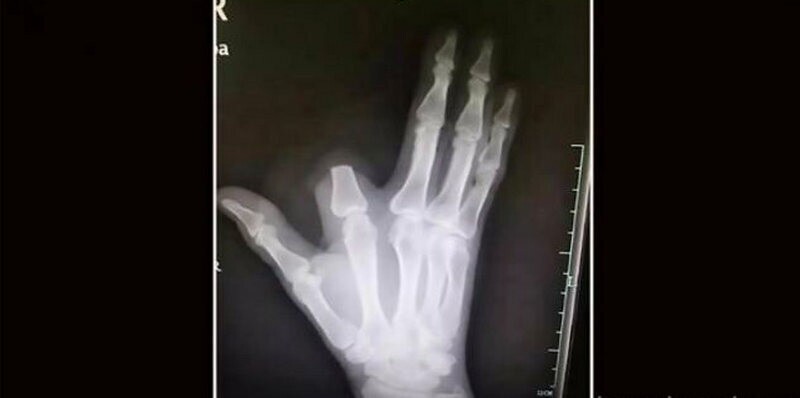

Мужчина решил себе отрезать палец после укуса змеи, однако врач сказал, что это было необязательно